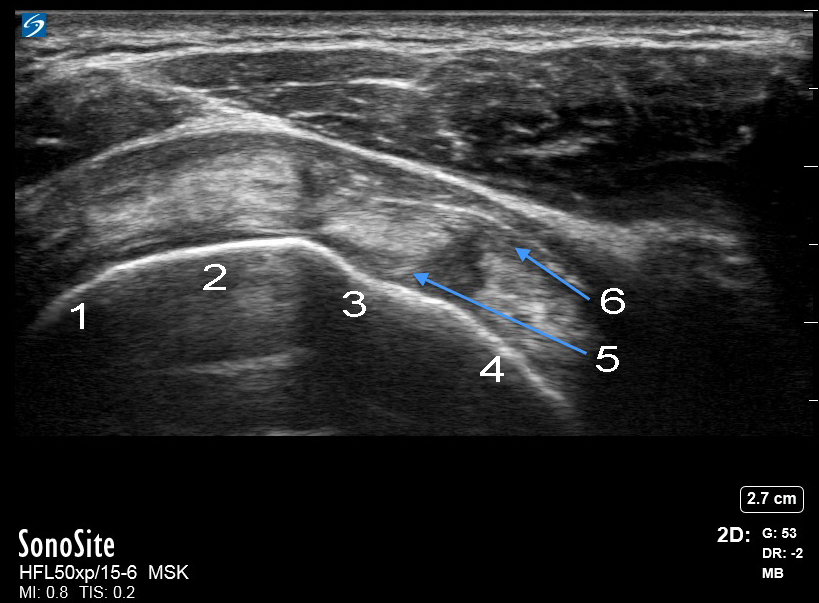

肩袖间隙横轴图像

冈下肌

冈上肌

二头肌腱 (BT)

肩胛下肌

上盂肱韧带 (SGHL)

喙肱韧带 (CHL)